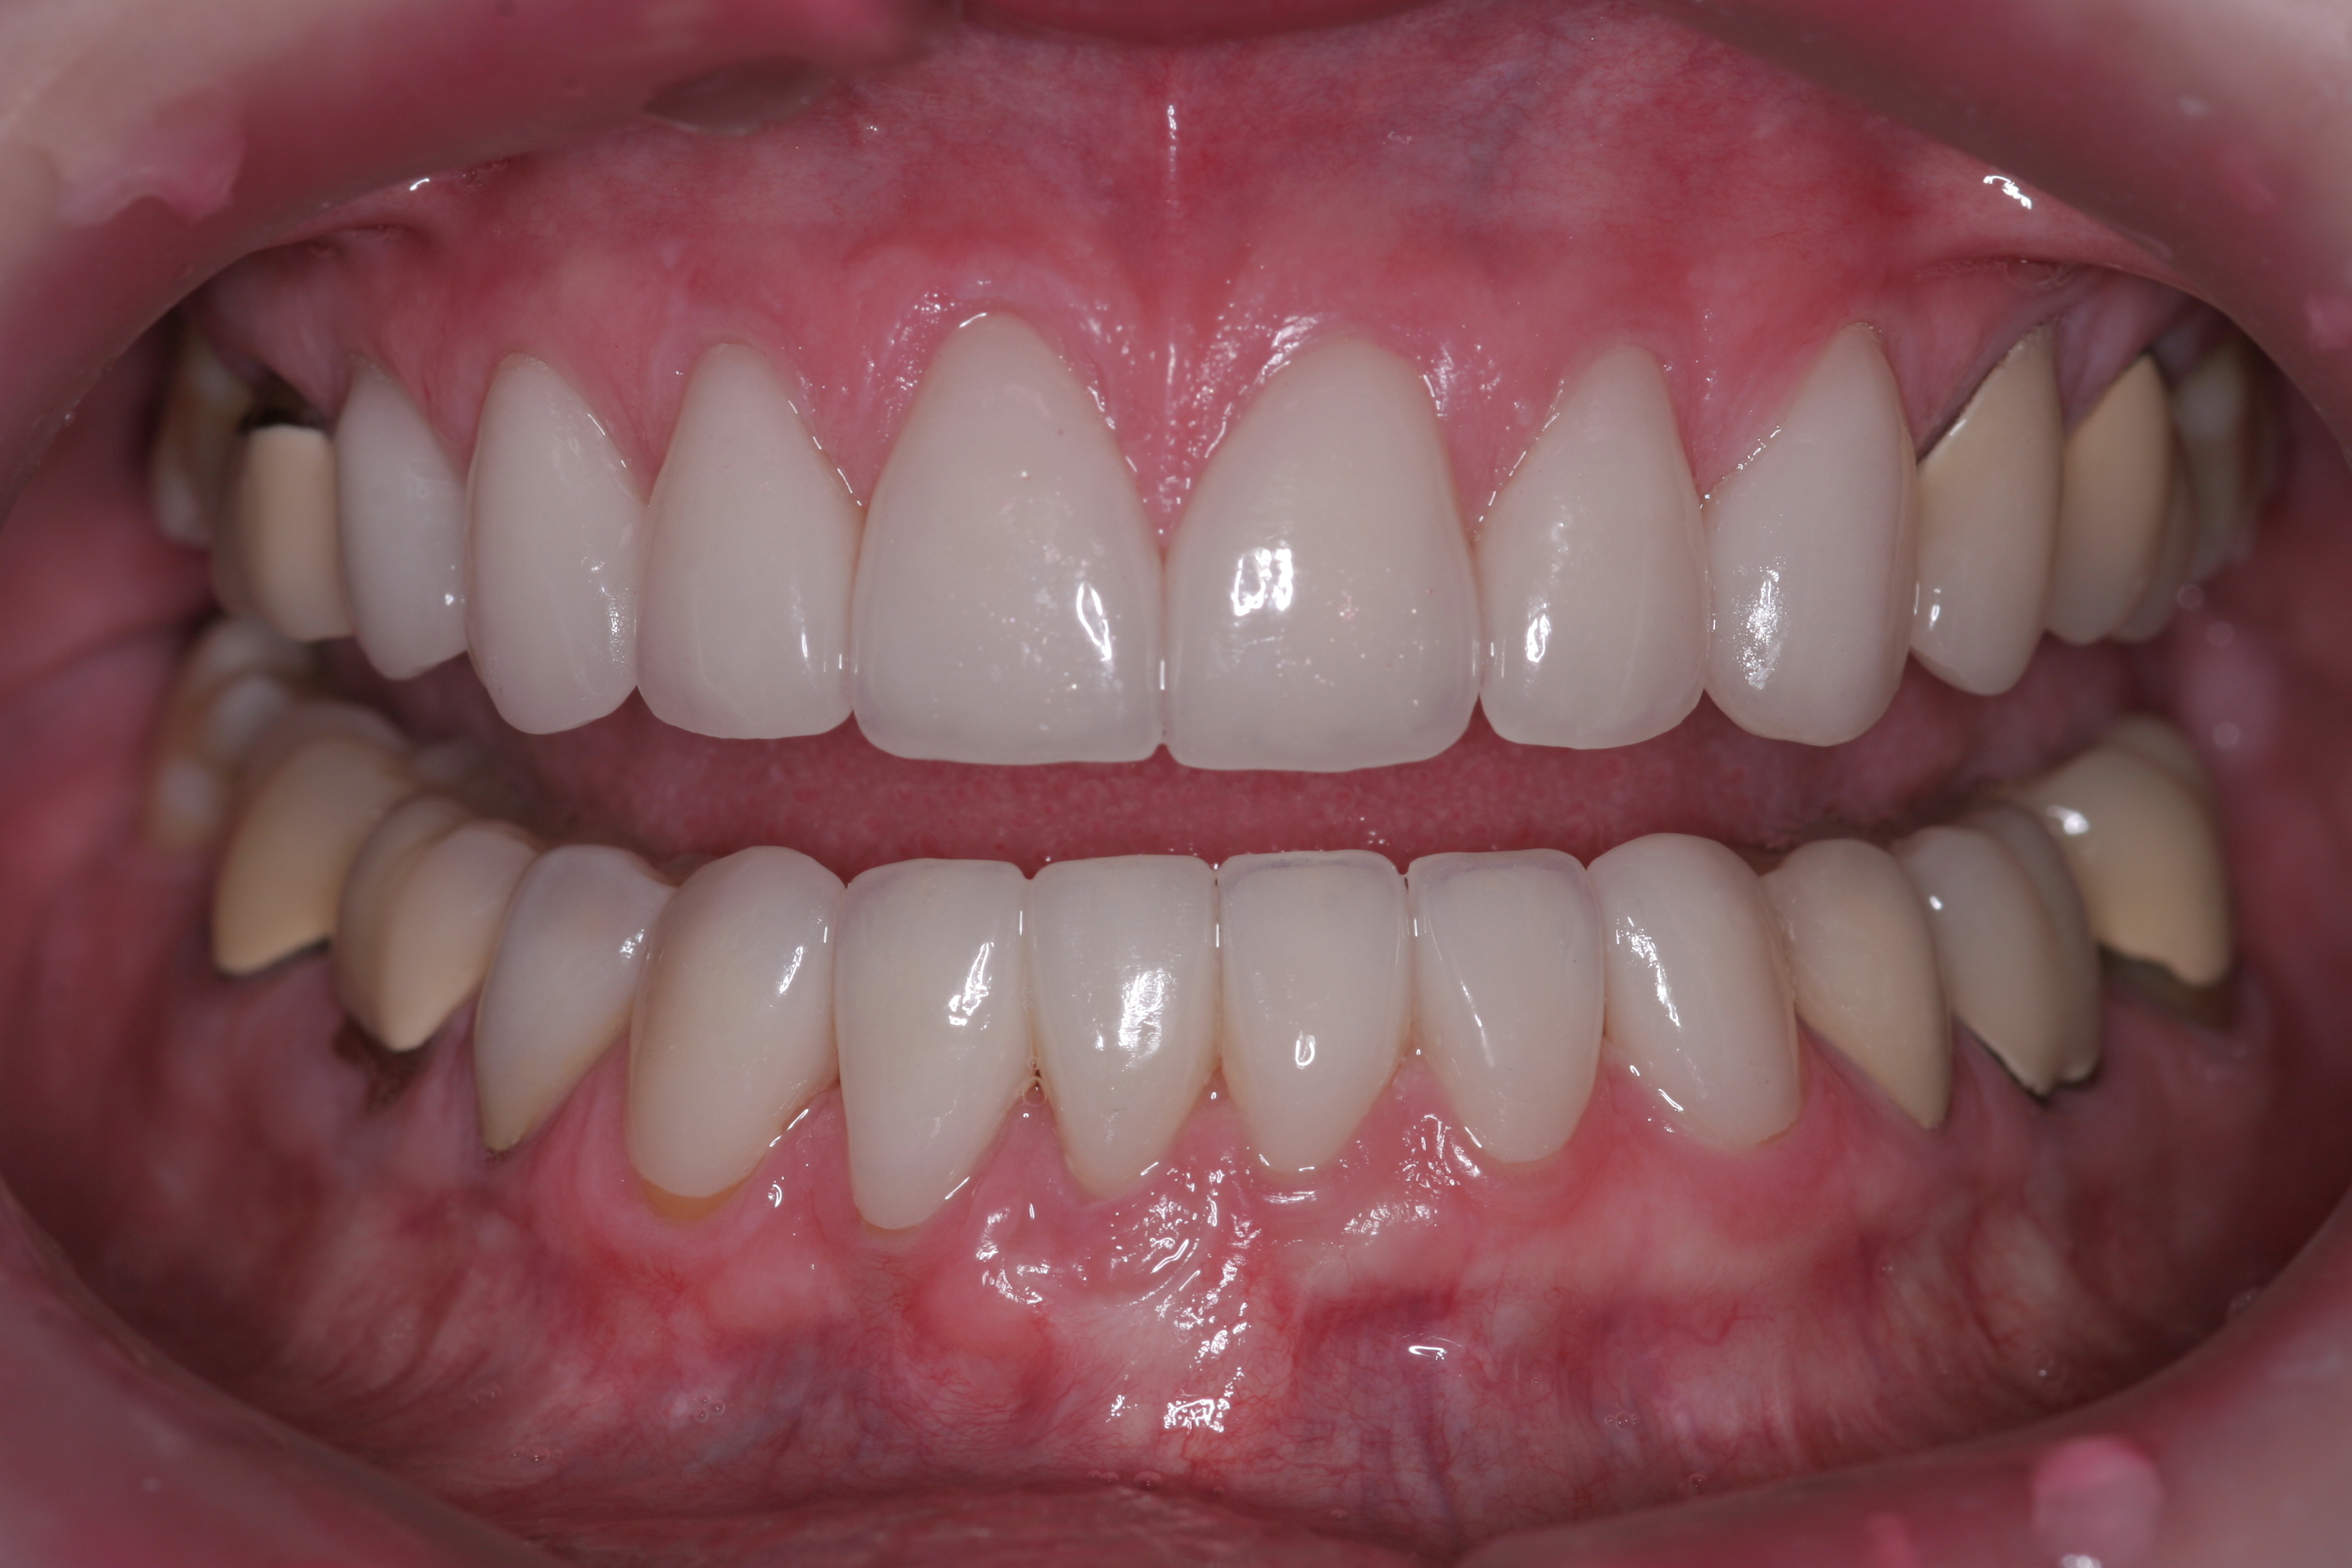

Treatment for this patient included posterior reductive equilibration and additive anterior equilibration (restoration) to eliminate the CR/MIP interferences and to meet the requirements of occlusal stability. Teeth Nos. 5 through 11 and 22 through 27 were prepared for full-coverage lithium-disilicate restorations. Crestal bone heights were evaluated. Soft-tissue crown lengthening was performed on the maxillary anterior teeth by a soft-tissue diode as needed. The esthetic, functional, and phonetic changes were evaluated and confirmed in the provisional restorative phase (Figure 17 through Figure 21).

Once approved, impressions of the provisionals were taken so the laboratory could precisely copy the 3D position of the anterior teeth as successfully proven in the provisionals. The postoperative result and final functional photographs are shown in Figure 22 through Figure 29. Posterior treatment can now be completed in segments as necessary. Posterior morphology will be developed in harmony with the now corrected anterior contour and functional parameters. The fulfillment of the previously mentioned requirements of occlusal stability were evaluated and refined in the final restorations. The patient was placed in a posttreatment dual-arch B splint appliance to help manage any further parafunctional forces should they occur.

(22.) The final restorations, which reflect the changes modeled through the provisional phase.

Figure 22

(23.) The final restorations, which reflect the changes modeled through the provisional phase.

Figure 23

(24.) The final restorations, which reflect the changes modeled through the provisional phase.

Figure 24

(25.) The final restorations, which reflect the changes modeled through the provisional phase.

Figure 25

(26.) The final restorations, which reflect the changes modeled through the provisional phase.

Figure 26

(27.) The final restorations, which reflect the changes modeled through the provisional phase.

Figure 27

(28.) The final restorations, which reflect the changes modeled through the provisional phase.

Figure 28

(29.) The final restorations, which reflect the changes modeled through the provisional phase.

Figure 29